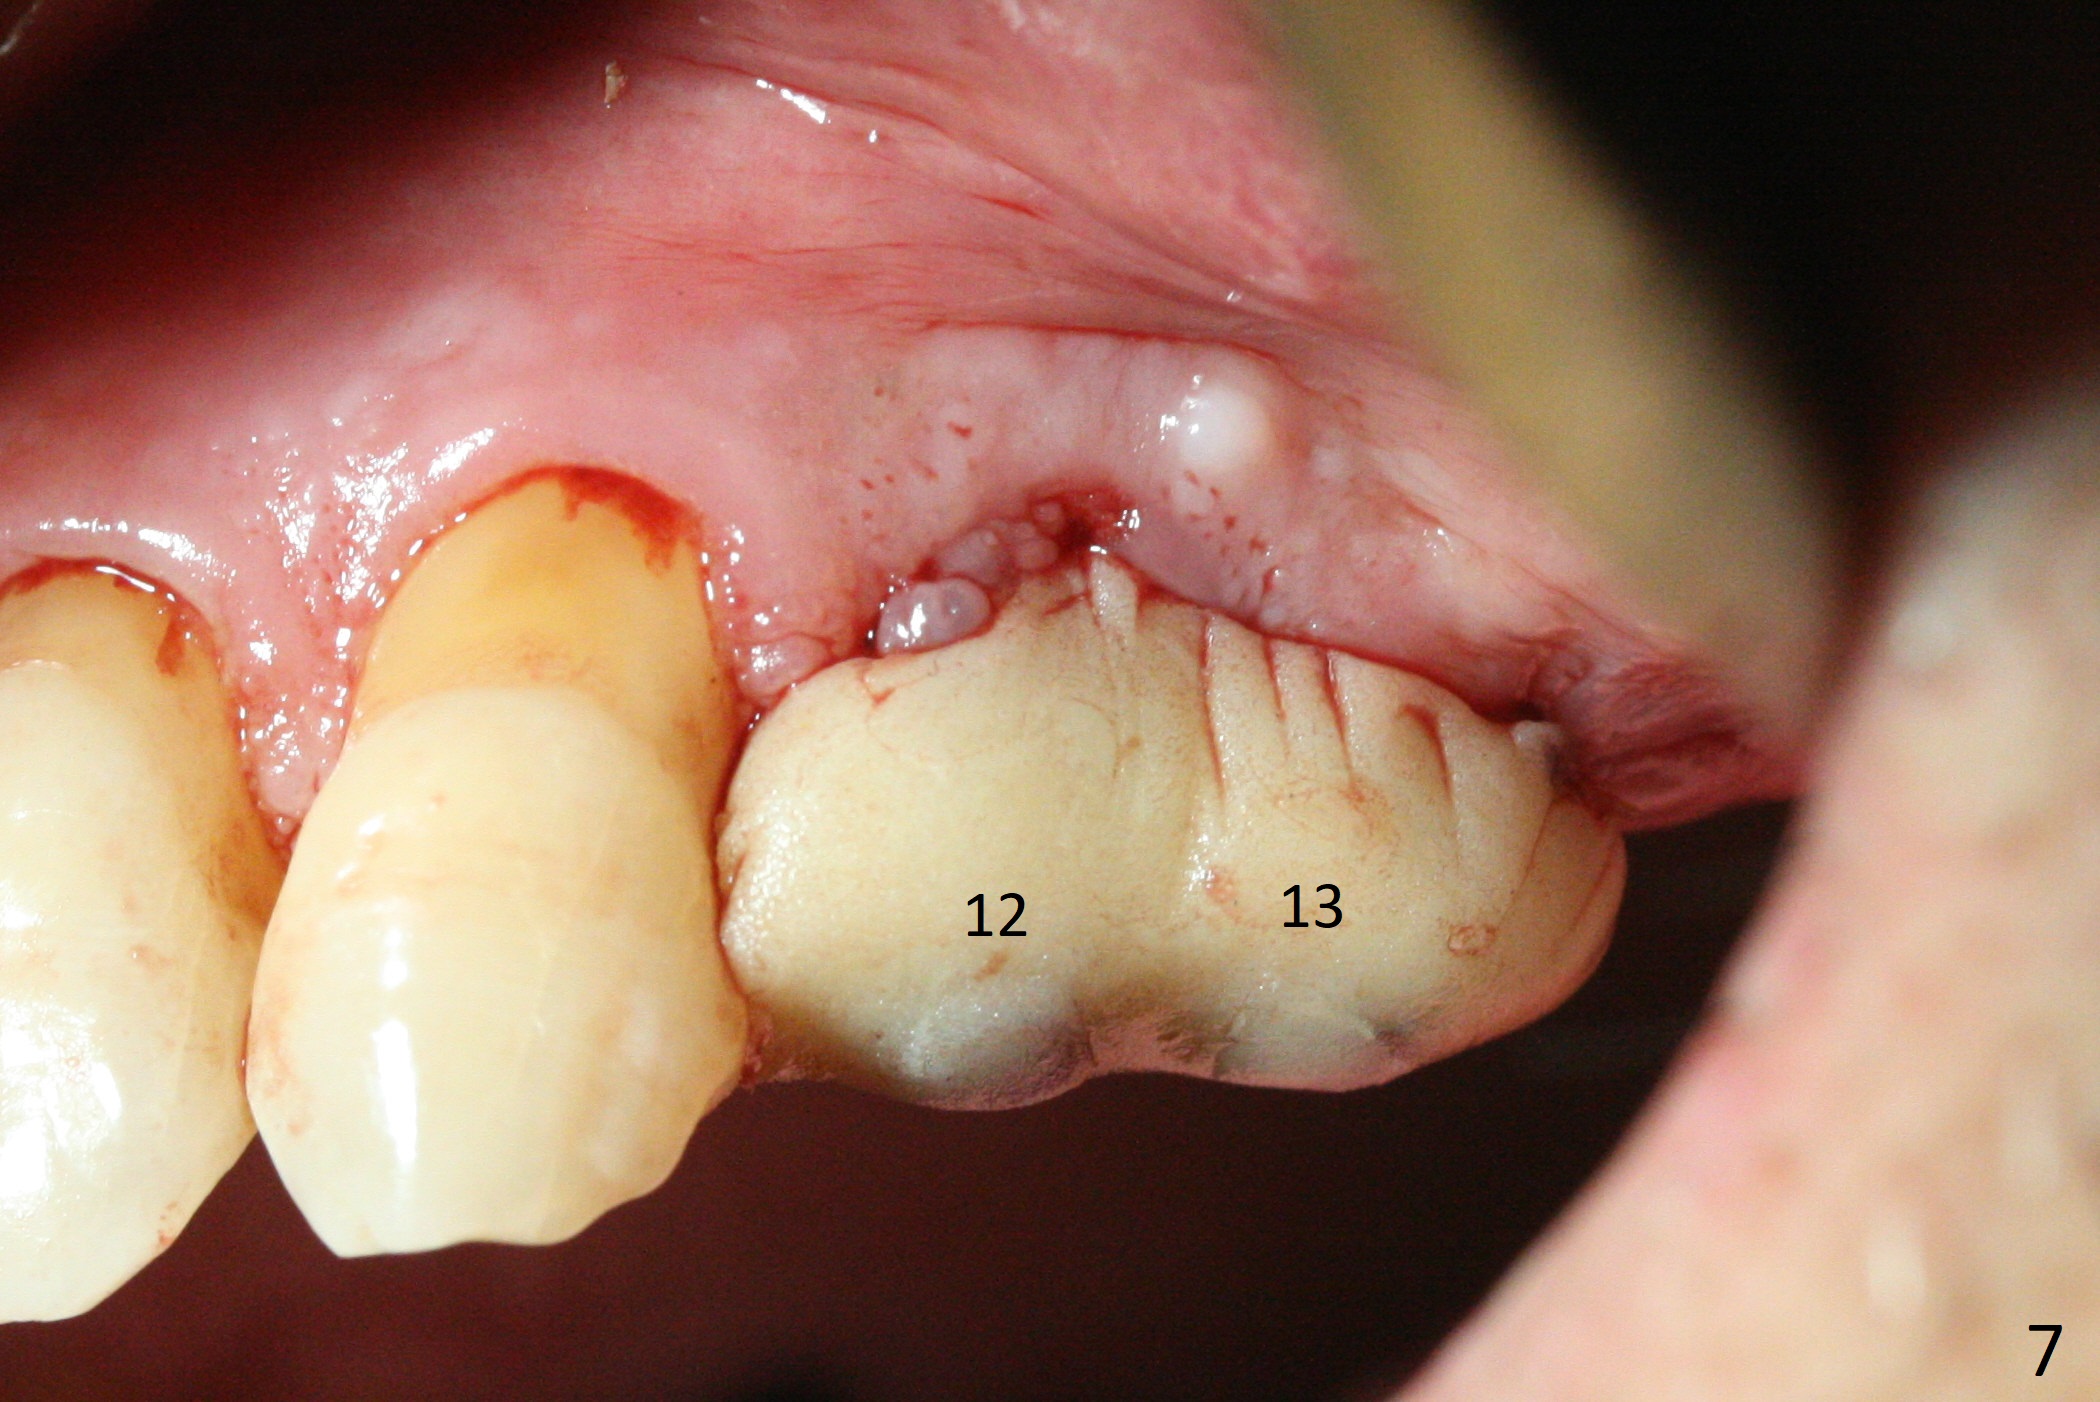

The buccal gingiva at #12 with vertical root fracture looks unhealthy (Fig.1). Osteotomy at #13 is initiated prior to #12 extraction. In fact the osteotomy happens in the extensive defect associated with #12 (Fig.2 red dashed line). To obtain primary stability, the osteotomy at #12 needs to be long, while that at #13 needs two-pointed fixation (Fig.3 *). After adjustment of trajectory at #12 and increase in diameter of the osteotomy at #13 (Fig.4), a 3.8x15 and 3.8x10 mm implants are placed (Fig.5). Following adjustment of implant depth (Fig.6), the implant at #12 becomes loose, while that at #13 tightens. With placement of abutments, an immediate splinted provisional is locked in place to stabilize the loose implant at #12 (Fig.7). The patient complains of cold sensitivity in the upper left quadrant, possibly related to the fact that the implant at #12 is close to the apex of the tooth #11. The position and trajectory of the initial osteotomies should be changed as shown in Fig.8 (white lines, as compared to Fig.2). There is no sensitivity 1 month postop. Impression is taken 4 months postop (Fig.9) after #13 mesiobuccal margin prep. The implants were placed too close to each other. The abutment screw at #13 is retightened 8 months post cementation. There appears no bone loss 9 months post cementation (Fig.10), while the tooth #11 has periapical infection with DL caries 1 year 7 months post cementation (Fig.11).